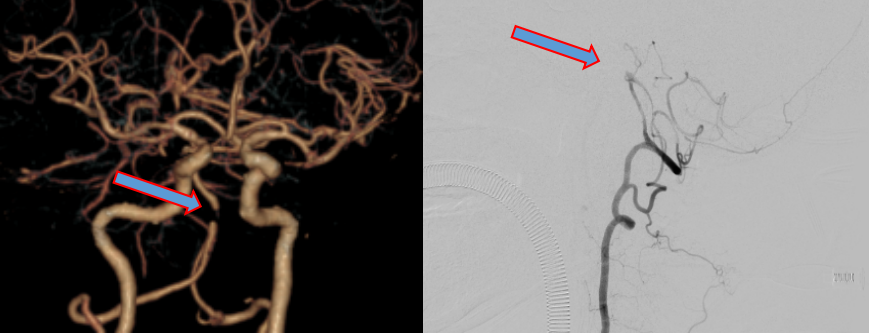

头颅CTA及DSA   脑血管造影显影基底动脉闭塞(箭头所指)

神经中心武剑主任带领团队深入分析及研究病情,充分细致评估,如脑动脉造影术、高分辨率核磁共振等检查,结果发现闭塞处远近端边缘有重要分支发出,这种分支均有重要功能,一旦闭塞会并发严重神经功能障碍。特别是在术中球囊扩张时,既要扩出通道亦不能因扩张产生“雪犁”现象堵塞分支,这进一步增加了手术难度及风险,介入团队武剑、冯新红、张小峰、付伟、王也、沈懿等人多次讨论手术方案及围手术期管理,制定了多套方案及可能出现并发症等应对措施,最终介入团队在武剑主任带领下,决定给予患者行基底动脉再通术。手术由张小峰主刀沈懿助手共同完成。